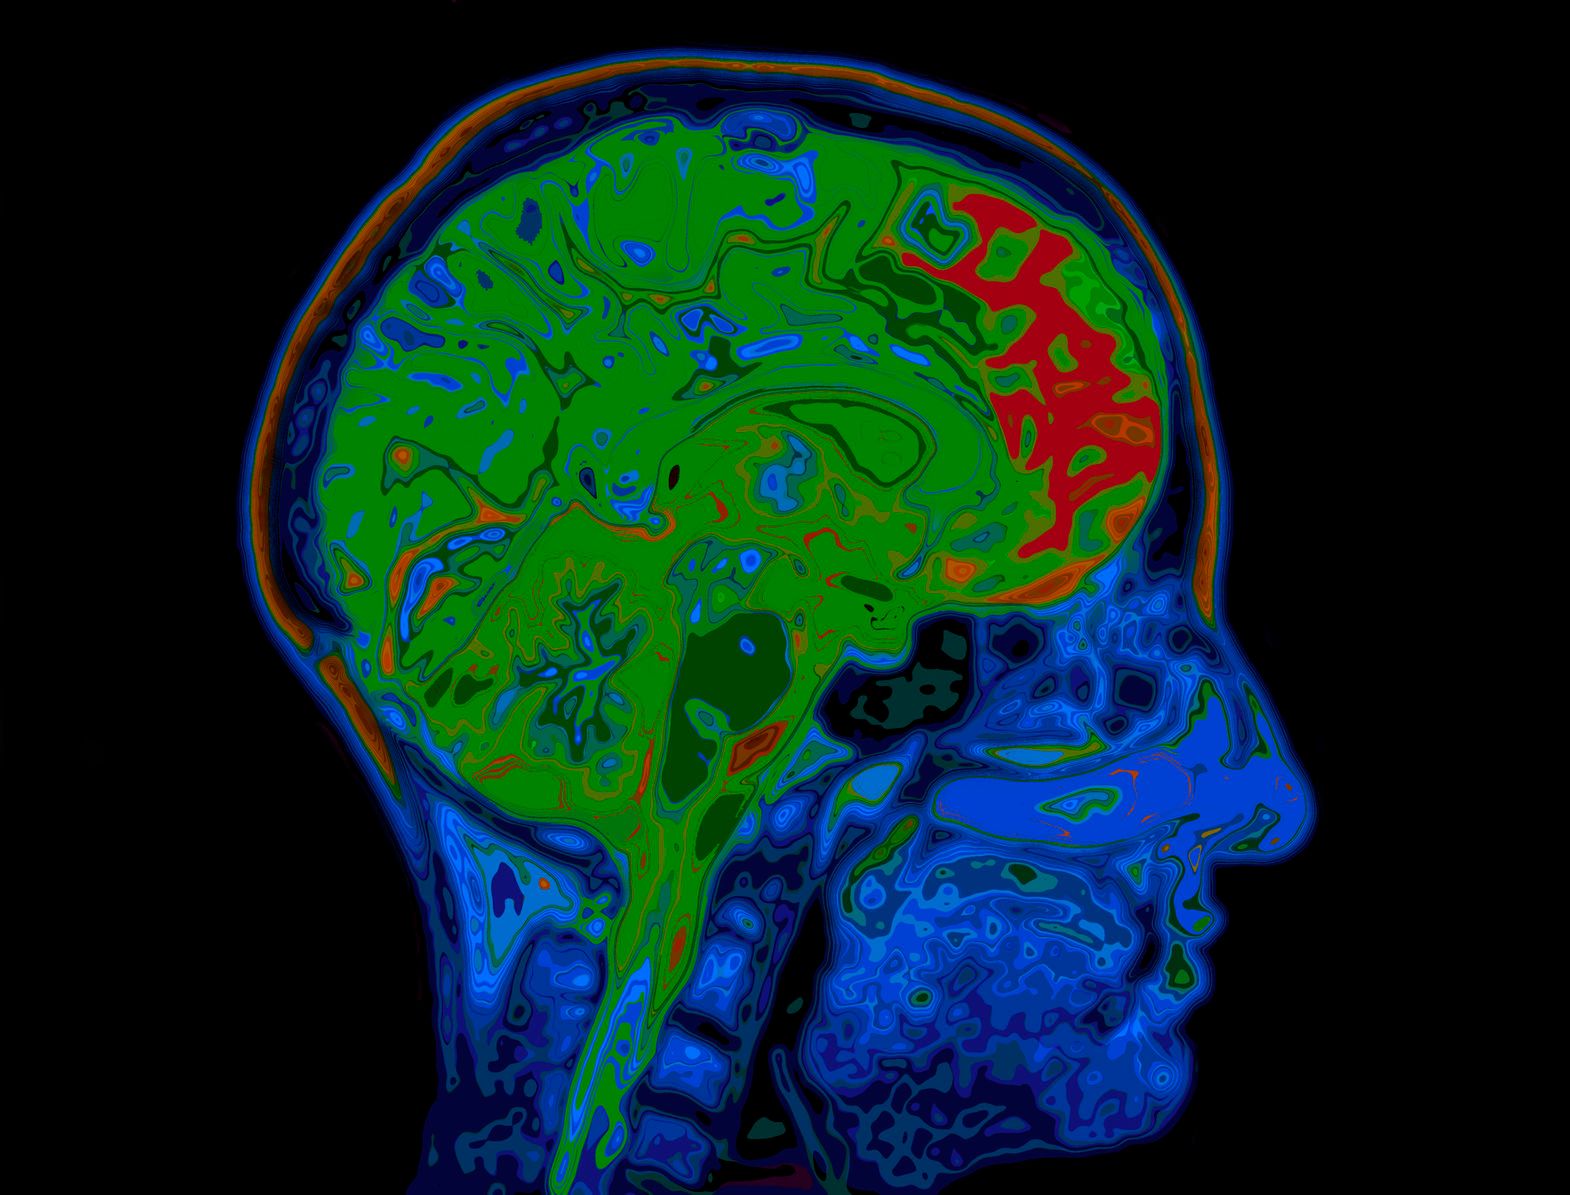

Co zabija nasze komórki mózgowe?

Przez lata funkcjonował mit, że człowiek wykorzystuje tylko 10 proc. swojego mózgu. Teoria została obalona. Wiadomo, że czynniki wpływające na inteligencję mogą polepszyć się wraz z treningiem. Ostatnie badania informują nas o jeszcze jednym ważnym aspekcie: co zabija nasze komórki mózgowe? Odpowiedź cię zaskoczy.

Komórki mózgowe

Do niedawna funkcjonowała popularna teoria, że nie ma limitów co do ilości komórek mózgowych. A wraz z dorastaniem, zwiększa się ich ilość, proces ten nazwano neurogenezą. Hipokamp struktura mózgowa o szczególnym znaczeniu dla procesów pamięciowych. Jego rola nie ogranicza się jedynie do przechowywania informacji na temat różnych zdarzeń z przeszłości. Odpowiada m.in.: za rozwój emocji, wspomnień, pamięci. Neurogeneza "rywalizuje" o przeżycie.

W efekcie niszczone są komórki mózgowe. Winę ponoszą trzy czynniki, popularne i często stosowane w życiu codziennym.